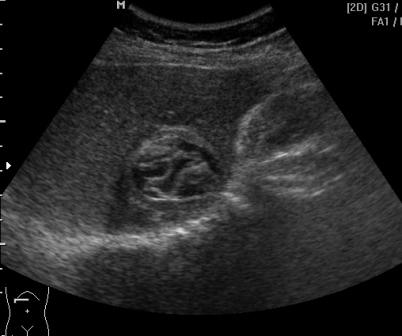

Бабушка из терапевтического отделения, которую беспокоит боль в правом подреберье.

Неужели паразитарная киста?

Да, эхонококк.Диагноз подтвержден методом ИФА. Оперативное лечение не показано. Было назначено консервативное лечение. Разместила больше не как загадку (картинка как из учебника), а потому что "красотой" захотелось поделиться :) .

У бабушки 30 котов.